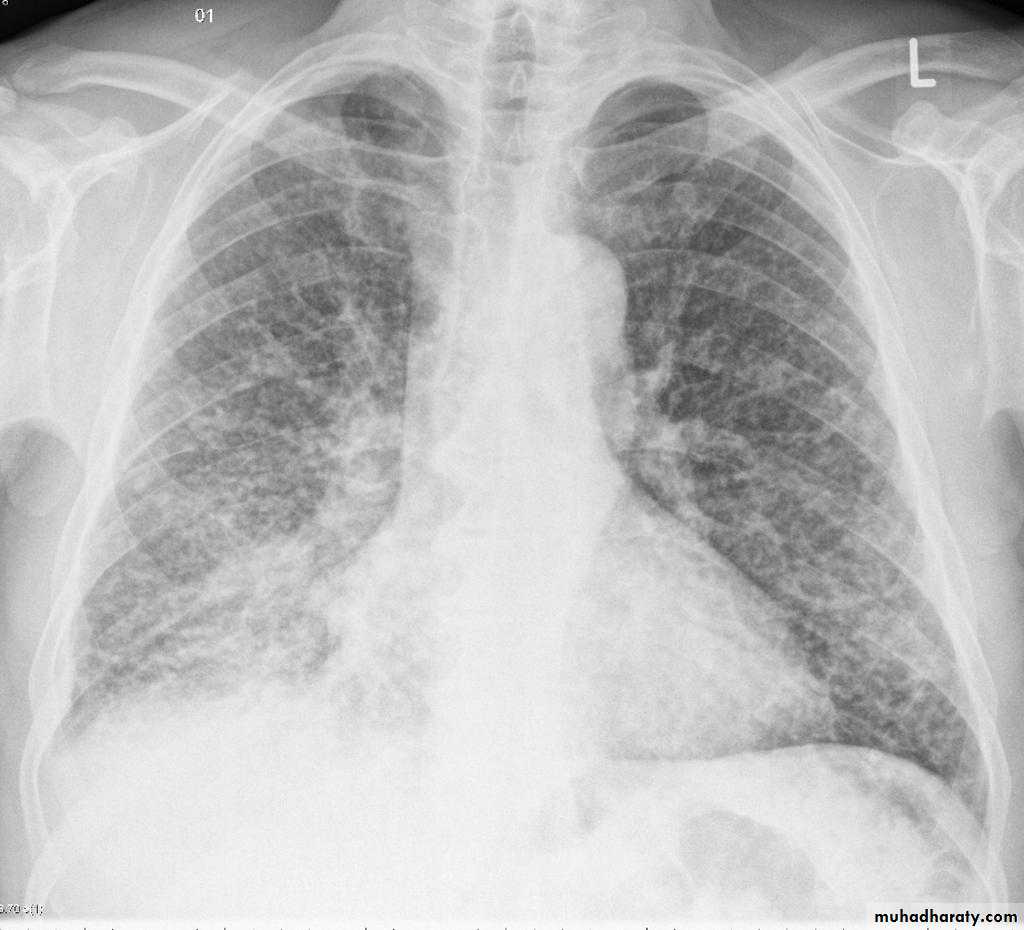

Miliary TBBilateral diffuse tiney nodules1-3 mm in diameter uniform in size and uniformly distributed involve whole lung fields.

miliary TB